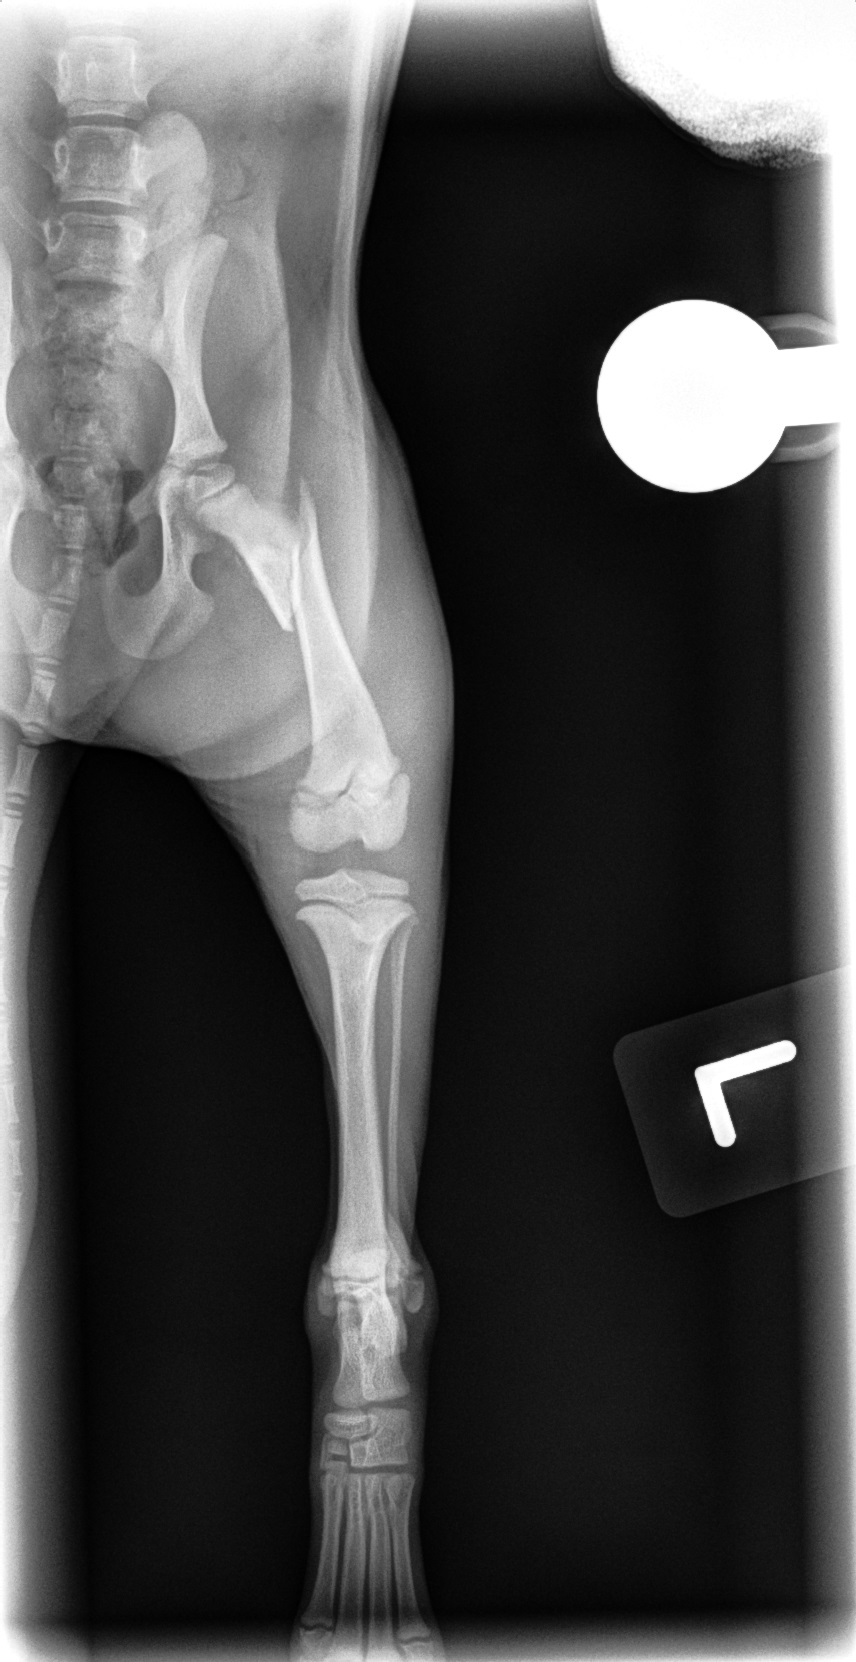

Femur Fracture Before

Fracture Repair

We provide surgical fracture repair for many types of broken bones. Treatment plans are individualized based on the location and complexity of the fracture, your pet’s age and size, and overall health.